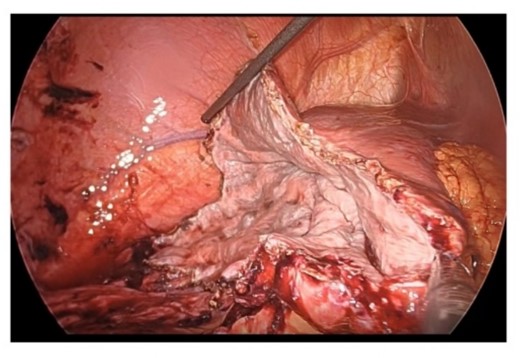

From these findings, we made the diagnosis of ruptured simple liver cyst and performed laparoscopic liver cyst fenestration and irrigation drainage 1 week after his admission to our hospital. A large hepatic cyst was found from the right abdomen to the right diaphragm. A dark red fluid suspected to be the content of the ruptured cyst was observed. We perforated the cyst capsule and 2500 ml of bloody fluid was drained. We resected the cystic wall as much as possible (Fig. 4). Postoperatively, paralytic ileus occurred but it was treated conservatively. The patient was transferred back to the previous hospital for the further treatment of the joint fracture on postoperative day 24.

Resection in the cystic wall, remaining 2 cm on the liver side was left.